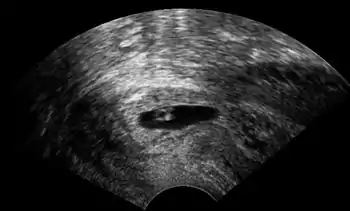

Author: Jesper Agrell

Ultrasonography of a cervical pregnancy Full text | Download doi: 10.15347/WJM/2014.011